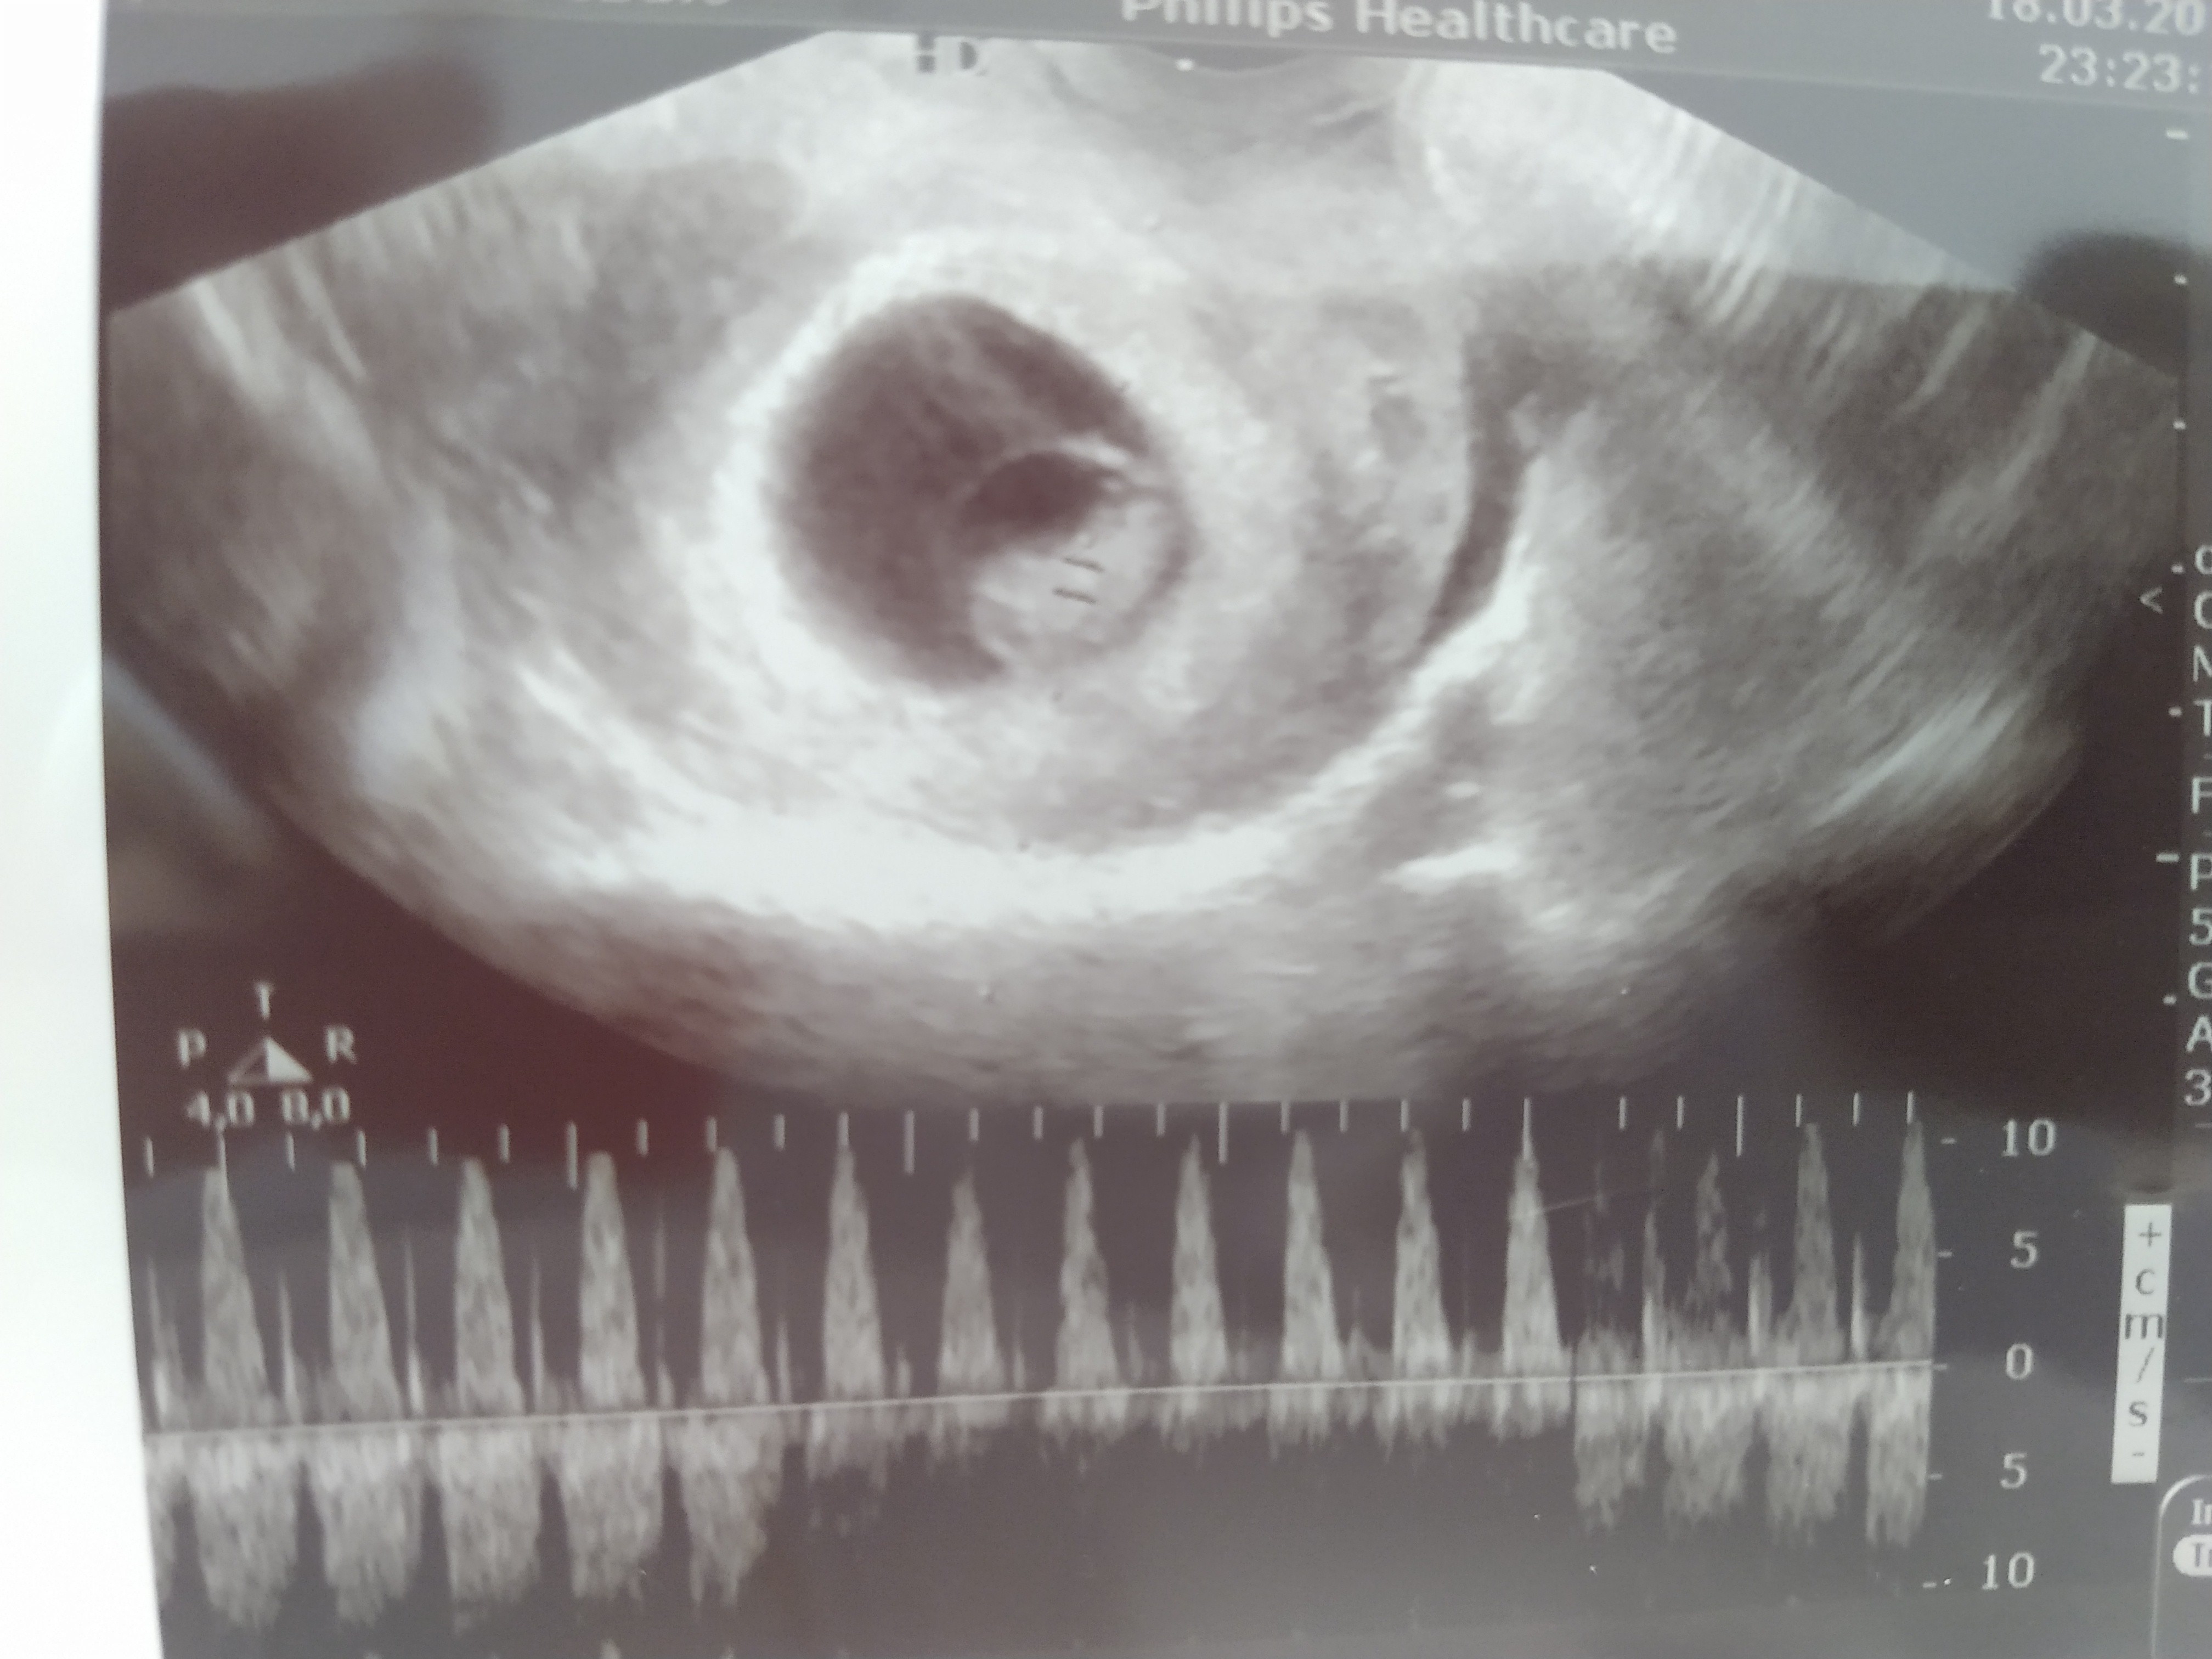

Tak,tak już miał 1,5 cm we wtorek. Słyszałam serduszko :) . Dziś zaczynam 8 tydzień. Wymiary wg USG zgadzają się z tymi z OM. Jeszcze muszę brać progresteron ale wszystko jest na dobrej drodze. A jak u Ciebie?